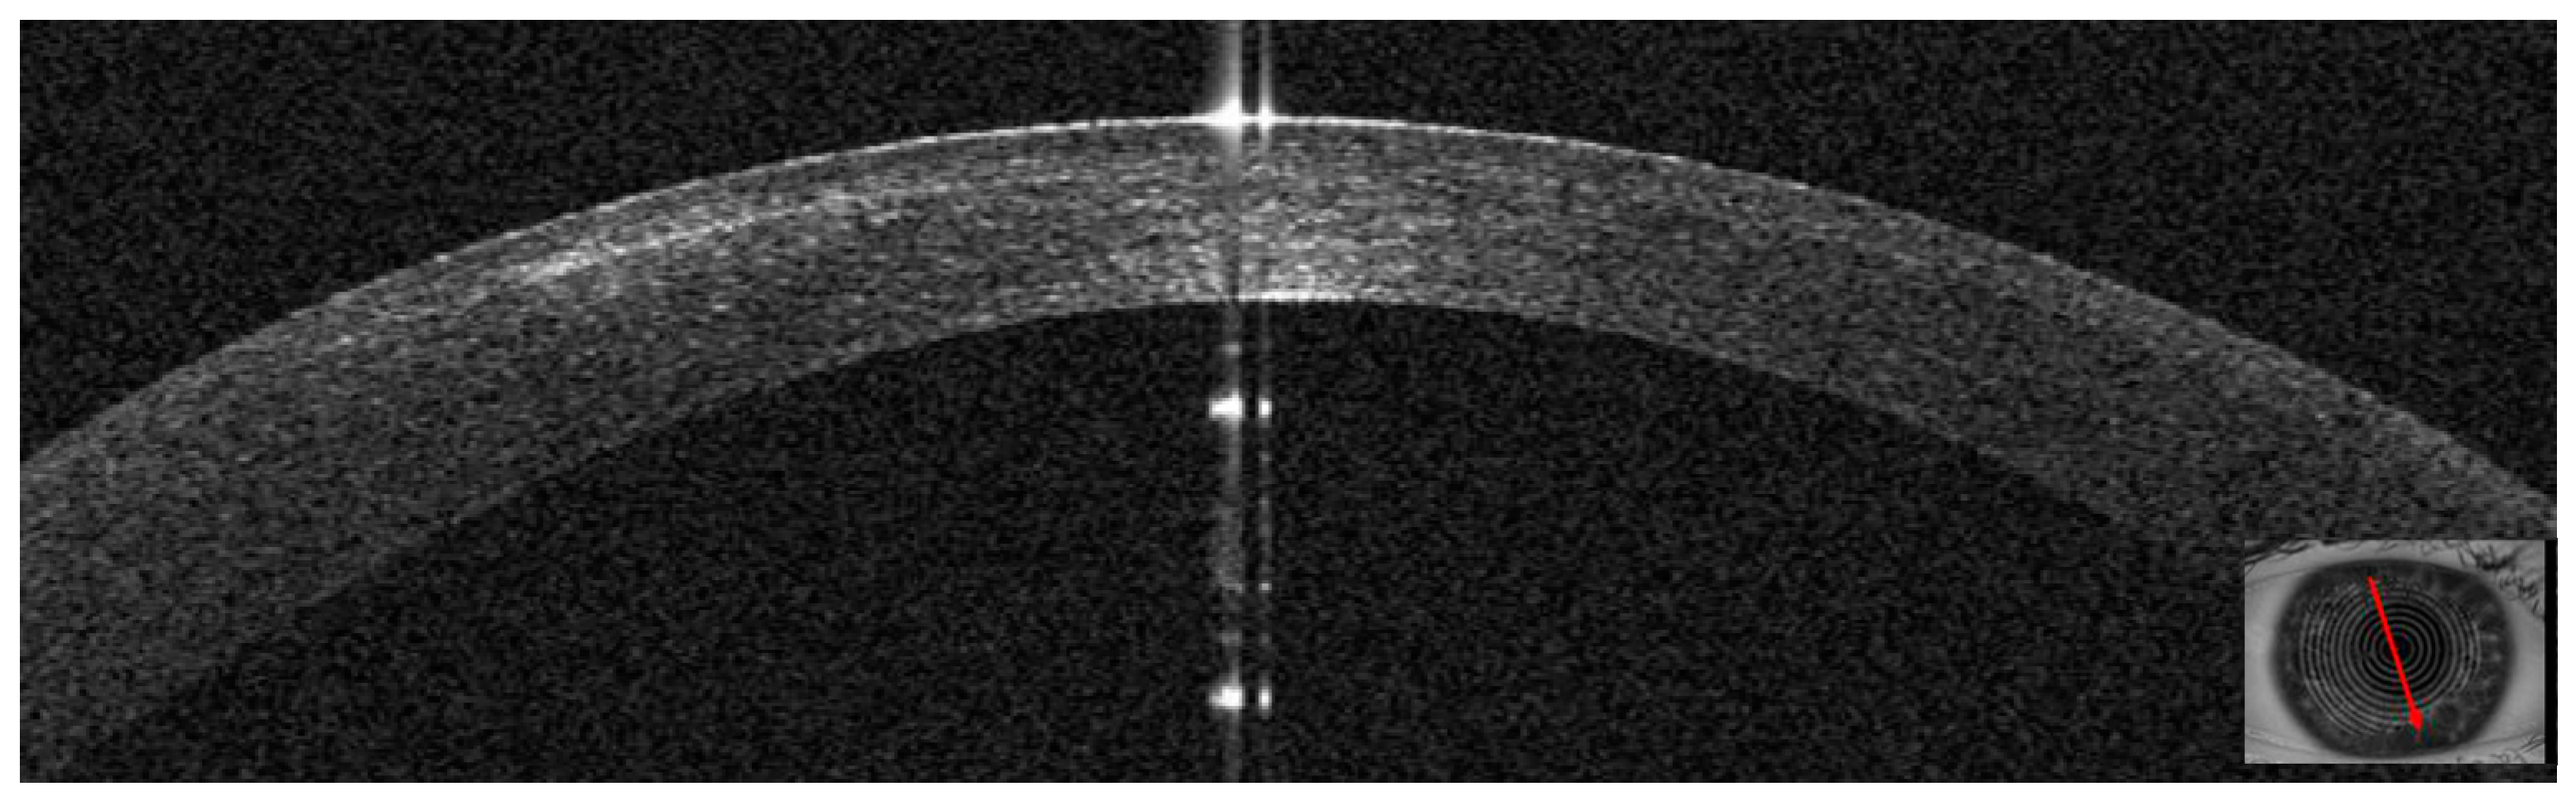

3.2. Patient #2